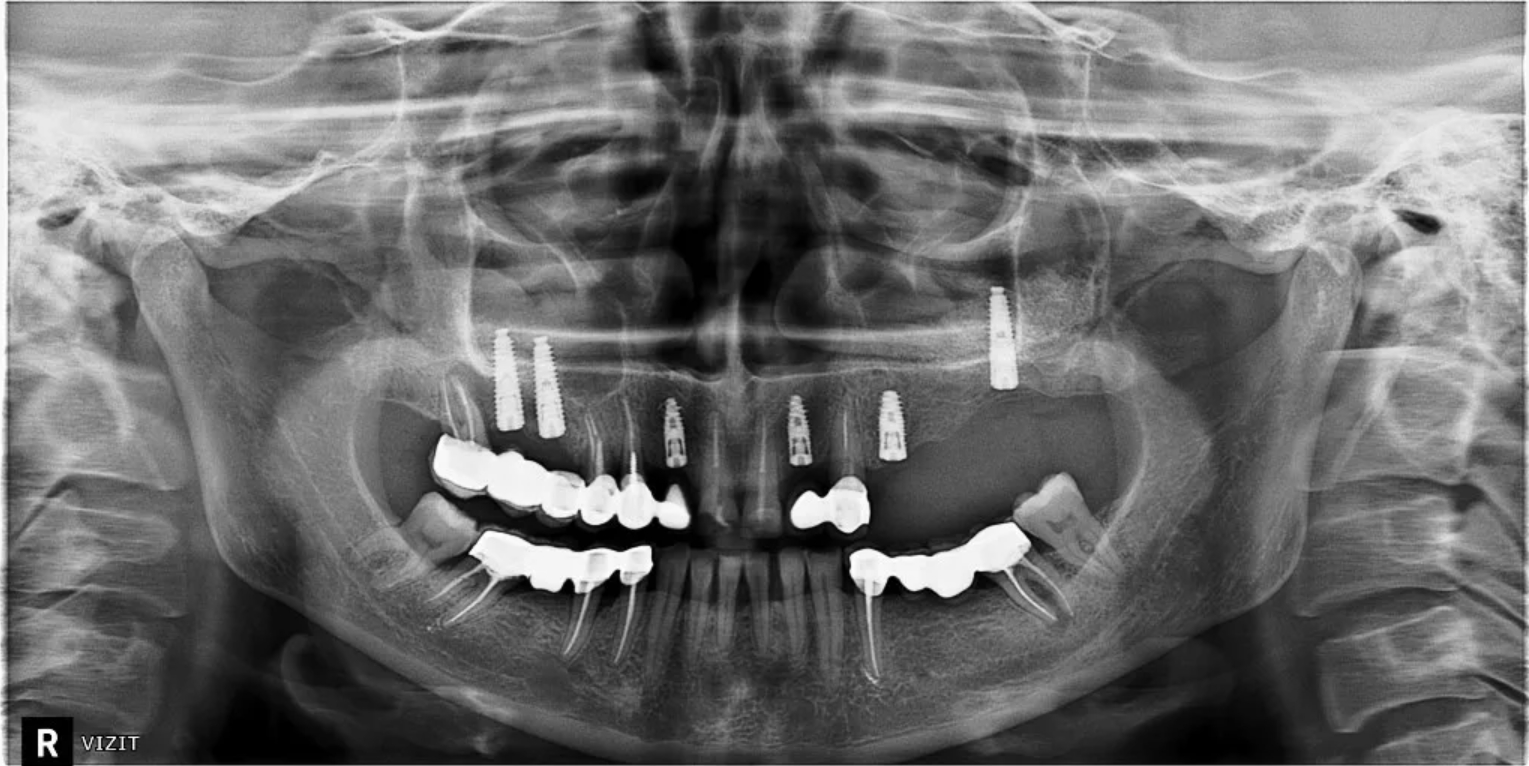

Исследование на рентгене после имплантации зубов

Раздел: Снимки-откровения